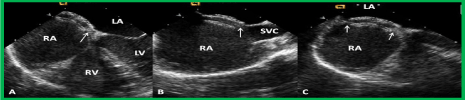

Figure 17. Selected video frames from a trans-esophageal echocardiogram following the implantation of an Amplatzer Septal Occluder to occlude an atrial septal defect, demonstrating the position of both disks in four chamber (A), bi-caval (B) and long axis (C) views. Note that the rims of the defect (thin arrows) are sandwiched between the left atrial (LA) and right atrial (RA) disks. LV, left ventricle; RV, right ventricle; SVC, superior vena cava. Reproduced from Reference 39.